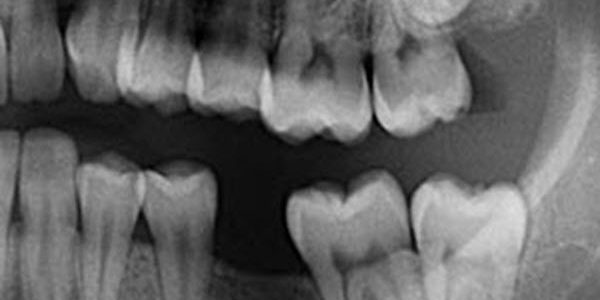

In some cases, wisdom teeth never erupt through the gums and are referred to as impacted (or impacted third molars). Impacted wisdom teeth are typically blocked from erupting due to the positioning of other teeth. If they remain impacted, they can cause pain and inflammation and infection may occur. In some cases, impacted teeth can cause damage to adjacent teeth. For these reasons, it is often necessary to have them surgically removed. Your dentist can advise the most appropriate time for extraction.